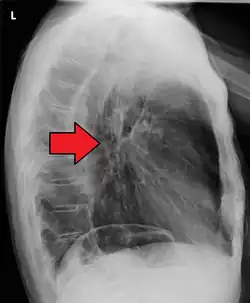

Although an occlusive tumor may be suspected on a barium swallow or barium meal, the diagnosis is best made with an examination using an endoscope. This involves the passing of a flexible tube with a light and camera down the esophagus and examining the wall, and is called an esophagogastroduodenoscopy. Biopsies taken of suspicious lesions are then examined histologically for signs of malignancy.

Additional testing is needed to assess how much the cancer has spread (see § Staging, below). Computed tomography (CT) of the chest, abdomen and pelvis can evaluate whether the cancer has spread to adjacent tissues or distant organs (especially liver and lymph nodes). The sensitivity of a CT scan is limited by its ability to detect masses (e.g. enlarged lymph nodes or involved organs) generally larger than 1 cm.[44][45] Positron emission tomography is also used to estimate the extent of the disease and is regarded as more precise than CT alone.[46] PET/MR as a novel modality has shown promising results in preoperative staging with fair feasibility and good correlation in comparison to PET/CT. It can enhance tissue differentiation with lowering the radiation dose to the patient.[47] Esophageal endoscopic ultrasound can provide staging information regarding the level of tumor invasion, and possible spread to regional lymph nodes.

The location of the tumor is generally measured by the distance from the teeth. The esophagus (25 cm or 10 in long) is commonly divided into three parts for purposes of determining the location. Adenocarcinomas tend to occur nearer the stomach and squamous cell carcinomas nearer the throat, but either may arise anywhere in the esophagus.